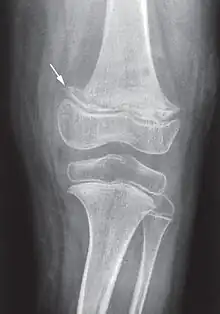

While many animals produce their own vitamin C, humans and a few others do not.[2] Vitamin C, an antioxidant, is required to make the building blocks for collagen, carnitine, and catecholamines, and assists the intestines in the absorption of iron from foods.[2][4][5] Diagnosis is typically based on outward appearance, X-rays, and improvement after treatment.[2]

Diagnosis is typically based on physical signs, X-rays, and improvement after treatment.[2]